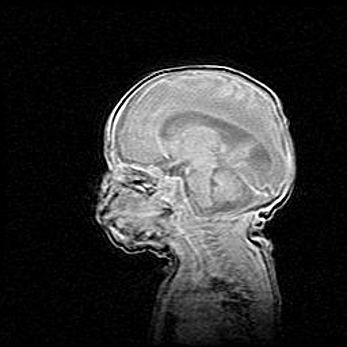

Аномалия Денди-Уокера. Признаки гипоплазии мозолистого тела.

Возраст: 5 месяцев 3 дня

Вес: 5550 г

Пол: мужской

Окружность головы: 39 см

Срок гестации: 40 недель

Аномалия Денди-Уокера – это порок развития головного мозга, для которого характерна триада симптомов: гипотрофия или аплазия червя мозжечка и/или полушарий мозжечка, расширение четвёртого желудочка с формированием ликворной кисты задней черепной ямки, гипертензионная гидроцефалия различной степени.

Гипоплазия мозолистого тела относится к дефектам внутриутробного этапа развития мозговой ткани, возникающим в процессе закладки структур головного мозга, что происходит на начальных этапах развития эмбриона.